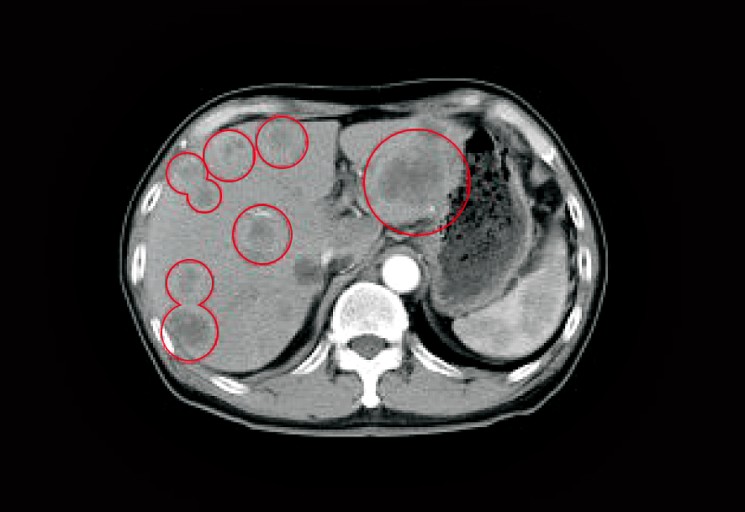

췌장염 증상 약 15cm의 길쭉한 모양을 하고 있는 췌장은 위의 바로 아래 뒤쪽에 위치해 있으며, 신장과 마찬가지로 배보다는 등 쪽에 붙어있어서 췌장에 문제가 있어서 복통이 발생하게 되면, 좌측 상복부 혹은 등 쪽에 고통이 발생할 가능성이 높아지게 됩니다.

담석

음주 다음으로 췌장염을 일으키기는 주요 원인이 바로 담석이다. 담석이 담관 끝부분 및 췌관을 막게 되면, 담즙과 췌장액이 제대로 분비하지 못하게 되어 염증이 발생하게 됩니다. 염증으로 인해 급성 췌장염이 나타나고, 제대로 치료를 받지 못하다 보면 만성췌장염으로 진행될 가능성이 높아지는데요.